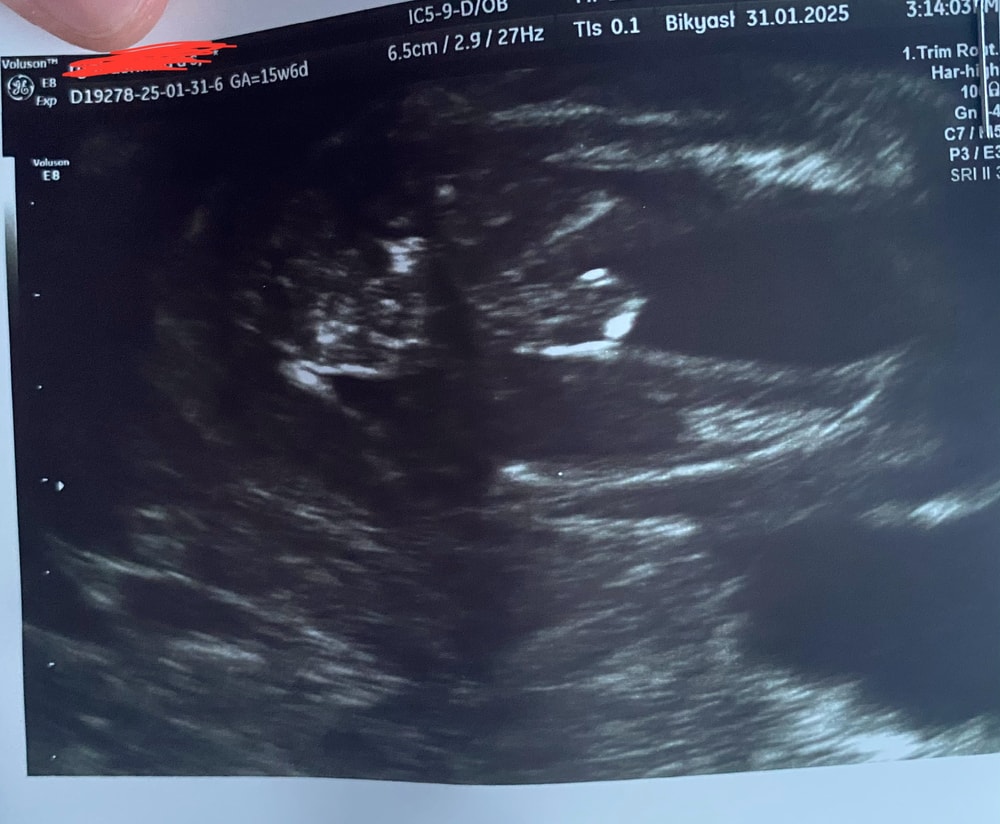

Девочки подскажите кто кого видит, срок 15 недель, узист сказала что не понятно((

Я почему то подумала, что мальчик. У нас просто с такого же ракурса фото, 15,6 недель было. Малой удачно повернулся и показал себя со всех сторон, узист на память фотку дал. Но было видно сразу, на 2 скрининге подтвердили, что мальчик. Вы можете либо ждать 2 скрининга, либо переделать в другом месте узи

действительно непонятно, то что между ног это пуповина скорее, а так не вижу в обще органы.

По этому фото я бы сказала мальчишка) но возможно это пуповина😁...но если судить по своим узи в эту беременность, когда смотрели такое положение, у нас ни разу ничего не болталось)